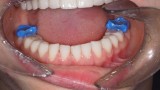

Po 6 miesiącach od zabiegu chirurgicznego rozpoczęto leczenie protetyczne mające na celu odbudowę prawidłowej anatomii zębów i odtworzenie utraconej funkcji żucia. W pierwszym etapie zaplanowano rekonstrukcję górnego łuku zębowego, wzorując się na wcześniej wykonanym woskowaniu i mock-upie. Preparacja przez mock-up pozwala na minimalnie traumatyczne szlifowanie, co jest szczególnie istotne w przypadkach takich jak przedstawiony, gdy już doszło do znacznej utraty tkanek na powierzchniach żujących zębów bocznych (16) (ryc. 30). Przed wykonaniem docelowych rekonstrukcji ceramicznych sprawdzono wyfrezowany z żywicy akrylopolimerowej (PMMA) prototyp z jednocześnie założonym na dolny łuk zębowy mock-upem (ryc. 31).

Następny etap leczenia polegał na adhezyjnym osadzeniu rekonstrukcji wykonanych z materiału E-max (Ivoclar, Liechtenstein). Po cementowaniu przystąpiono do preparacji zębów dolnego łuku zębowego. Pozostawienie wszystkich drugich zębów trzonowych w pierwotnym kształcie umożliwiło łatwą rejestrację pozycji żuchwy w RC przed rozpoczęciem preparacji, którą wykonano na twardym materiale (LuxaBite, DMG, Niemcy) (ryc. 32, 33). Po zakończeniu preparacji rejestrat zwarciowy powiększono o odcinek przedni, wykonano wyciski oraz zabezpieczono filary wcześniej przygotowanymi i podścielonymi uzupełnieniami z PMMA (ryc. 34-36). Podobnie jak w łuku górnym, w następnym etapie sprawdzono wewnątrzustnie prototyp rekonstrukcji wyfrezowany w PMMA, na którym wykonano niezbędne korekty zwarcia (ryc. 37, 38). Ostatni etap leczenia polegał na adhezyjnym cementowaniu rekonstrukcji dolnego łuku zębowego.